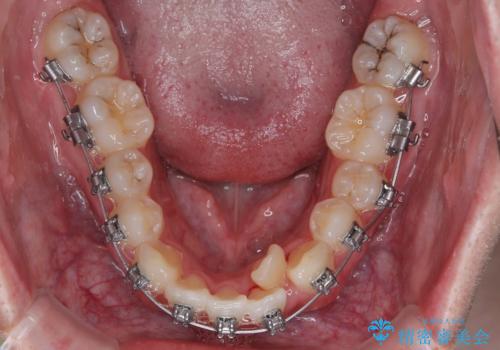

適切な診断と装置の選択により、1年という短期間でここまで改善できます。

見た目の美しさだけでなく、将来のむし歯や歯周病リスクを減らすことにもつながる治療です。